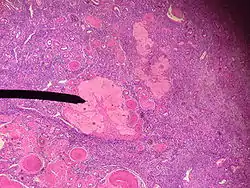

- Строение: 1) погибший овоцит первого порядка, 2) остатки блестящей оболочки, 3) остатки фолликулярного эпителия лучистого венца, 4) гипертрофированные интерстициальные клетки (текациты).

- Функции: уничтожение мутировавших овоцитов, предупреждение многоплодия, эндокринная (андрогены, эстрогены), регуляция циклических и возрастных инволюций молочной железы.